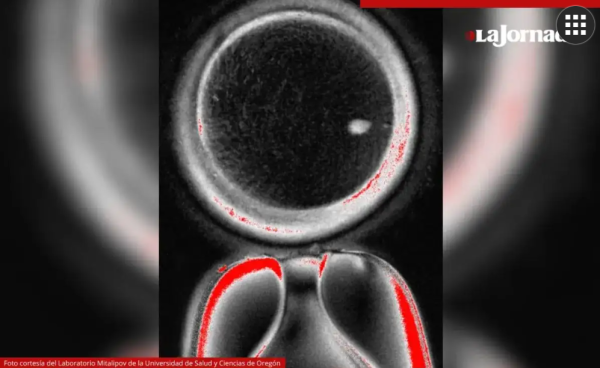

La investigación podría ser una respuesta a la infertilidad, que afecta a una de cada seis personas en el mundo. Foto cortesía del Laboratorio Mitalipov de la Universidad de Salud y Ciencias de Oregón

Crearon 82 ovocitos, que luego fueron fertilizados con esperma mediante fecundación in vitro (FIV).

Después de seis días, menos de 9 por ciento de los embriones se desarrollaron hasta el punto en que hipotéticamente podrían ser transferidos al útero en un proceso estándar de FIV.

Sin embargo, los embriones mostraron diversas anomalías, por lo que el experimento fue suspendido.